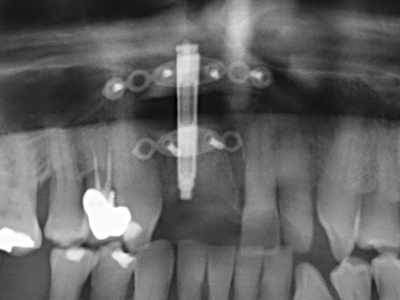

Como ya se ha demostrado en el pasado, básicamente cualquier procedimiento de cirugía de hueso representa una posible indicación para la cirugía piezoeléctrica. Así, la preparación del segmento móvil en la osteogénesis de distracción (fig. 23-25) y en la osteotomía de sándwich puede realizarse con piezas especiales, sin poner en peligro el suministro sanguíneo de la parte crestal, que resulta esencial para el éxito de ambas técnicas (González-García, Diniz-Freitas et al. 2008).